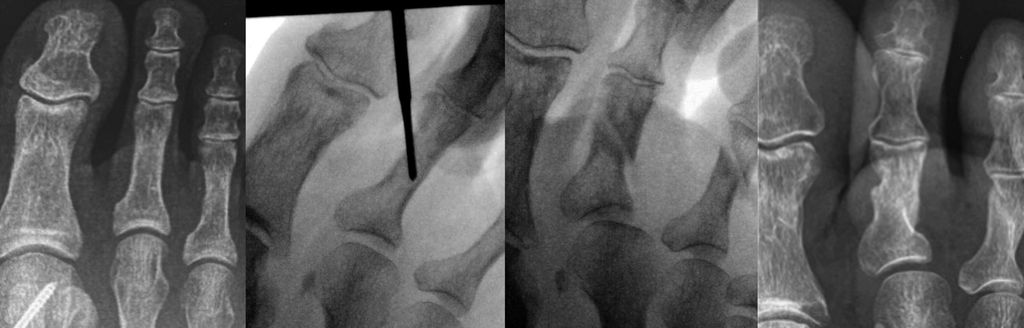

Bei der Korrektur der Kleinzehendeformitäten unterscheidet man zwischen Eingriffen an den Weichteilen und knöchernen Eingriffen.20 Eingriffe an den Weichteilen sind entweder Tenolysen oder Arthrolysen. Die infrage kommenden Sehnen sind die EDL(Extensor digitorum longus)-Sehne, die FDL(Flexor digitorum longus)- und die FDB(Flexor digitorum brevis)-Sehne. Kapsulotomien werden am Metatarsophalangealgelenk (MTP) dorsal, am proximalen Interphalangealgelenk (PIP) plantar und am distalen Interphalangealgelenk (DIP) durchgeführt.

Die Tenotomie der FDL- und der FDB-Sehne erfolgt jeweils medial oder lateral plantar über dem PIP- bzw. dem DIP-Gelenk. Die Zehe wird in Flexion gehalten und die Messerklinge parallel zur Unterfläche an die Basis der Mittelphalanx bzw. Endphalanx herangeführt. Die Klinge wird um 90° rotiert. Dadurch wird die Beugesehne durchtrennt. Zusätzlich muss meistens noch die Gelenkkapsel plantar perforiert werden, bis die Zehe im entsprechenden Gelenk gut gestreckt werden kann.

Die Tenotomie der EDL-Sehne erfolgt an der Streckseite. Auch hier wird die Messerklinge neben der Strecksehne parallel zum Fußrücken eingebracht und unter Drehung der Klinge die Sehne durchtrennt.

Die Kapsel des MTP-Gelenkes wird durch Perforation mit der Messerklinge von dorsal eröffnet.

Eine Hammerzehe oder auch mediale bzw. laterale Deviation kann mit perkutan durchgeführten Osteotomien mit der minimalinvasiven Fräse korrigiert werden. Bei einer Hammerzehenfehlstellung erfolgt nach Stichinzision unter der Basis der Grundphalanx bzw. dorsal an der Mittelphalanx, nach Abschieben der Weichteile mittels Elevatorium, mit der Fräse eine Kortikotomie unter Erhaltung der gegenüberliegenden Kortikalis. Dann kann durch Druck die Osteotomie geschlossen und damit die Korrektur erzielt werden. Falls über dem PIP-Gelenk noch eine Prominenz tastbar ist, wird diese über die dorsale Inzision mit der Fräse abgeschliffen.21,22

Isolierte Überlängen von Zehen können mit minimalinvasiven Osteotomien an der Grundphalanx sehr gut korrigiert werden (Abb. 6). Bei Fehlstellungen in der Transversalebene wird ebenfalls über eine Stichinzision in Höhe der Fehlstellung eine Kortikotomie durchgeführt und die Fehlstellung durch Schließen der Osteotomie korrigiert (Abb. 7).